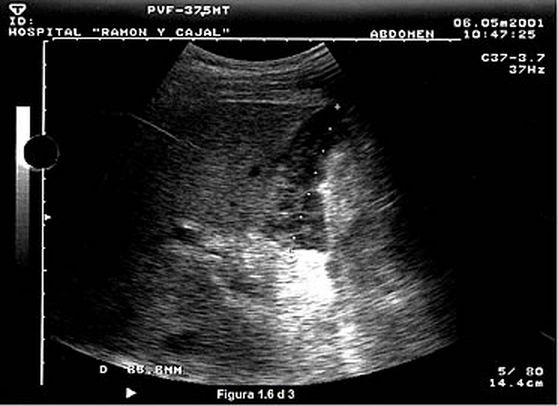

Colecciones líquidas Los hematomas son frecuentes y se suelen localizar a nivel perihepático como colecciones hipo o anecoicas que a medida que transcurren los días y el hematoma se organiza, adquieren un aspecto heterogéneo con áreas hiperecoicas alternando con otras hipoecoicas. |